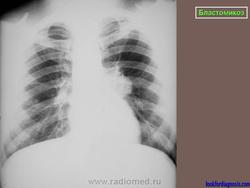

Рентгенологически отмечаются выраженные изменения лимфатических узлов средостения, очаговые инфильтраты, в некоторых из них развиваются каверны с неправильными контурами. При диссеминации процесс захватывает многие органы, эти формы часто заканчиваются гибелью больного.